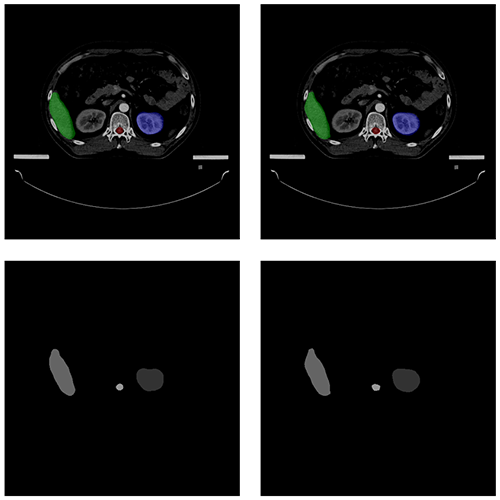

自動勾畫效果

AUTOMATIC CONTOURING

原圖

預測圖